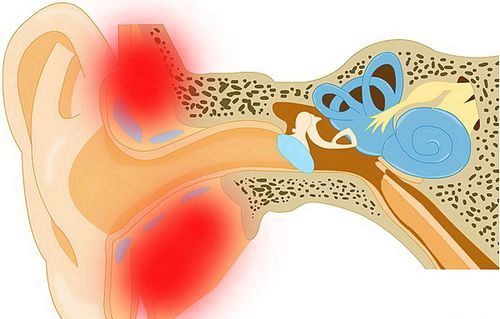

Часто простудні захворювання негативно впливають на органи середнього і внутрішнього вуха. Одним з найбільш поширених захворювань є тубоотит. Ця недуга приносить дуже сильний дискомфорт і гострий біль.

Запалення, утворене в ході евстахиита, може стати причинному потовщення слухової труби і зниження тиску всередині вуха. Наведені симптоми можуть привести до западання барабанної перетинки у внутрішнє порожнину вуха.

У багатьох випадках, симптоми гострого евстахиита починають проявлятися після інфікування грипом та гострими респіраторними захворюваннями, або під час сезонного катару верхніх дихальних шляхів .